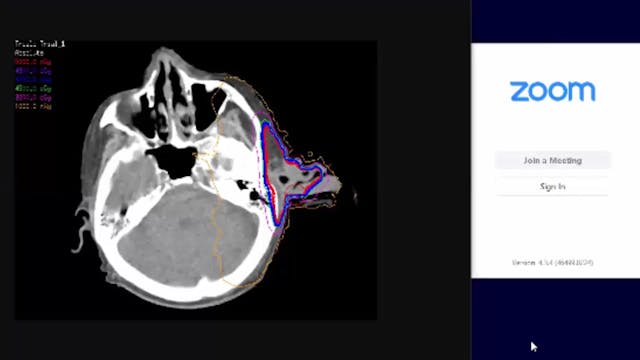

04/29/19 - Dr. David Sher - Radiation Oncology - Head and Neck US

Chartrounds US - Head and Neck Cancer